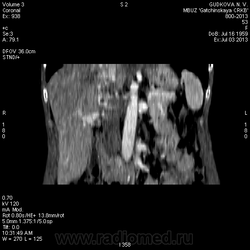

В артериальную фазу - интенсивное накопление контраста, как раз в области этого расширения, в 4-5 сегментах печени.Выше и ниже - идет неизмененная НПВ, без контраста (фаза артериальная!) В венозную фазу - небольшая гиперденсная зона перикавально в печени - и все.

На 3d-реконструкциях выглядит как кавернозная гемангиома, по форме напоминающая желчный пузырь (который я, кстати, не вижу, а УЗИсты описывают) Если это - ж.п., почему так интенсивно копит контраст, и вообще, расположение такое нетипичное?

Это нижняя полая. Заброс контраста в нижнюю полую вену и контрастирование веточек портальной вены в артериальную фазу бывает при неправильной технике проведения болюса. Посмотрите тут: http://www.radiographia.ru/sites/default/files/abdominal_ct_protocols.pdf

Заброс контраста в нижнюю полую в артериальную фазу может быть при пассивном венозном застое, как следствие перикардита или сердечной недостаточности.у меня один раз тоже такое было, голову сломала, но в Прокопе все же нашла.

Может быть это просто нормальное контрастирование нижней полой вены за счет почечных вен, а не заброс контрастного вещества?

Да, это нижняя полая вена.

Мелкую кисту в правой доле печени (S6) я нашел. Ее нет на представленных сканах(выложил то, что меня смутило), но, думаю, именно ее описывают УЗИсты. И размеры совпадают, и гипоэхогенность характерна для кисты.